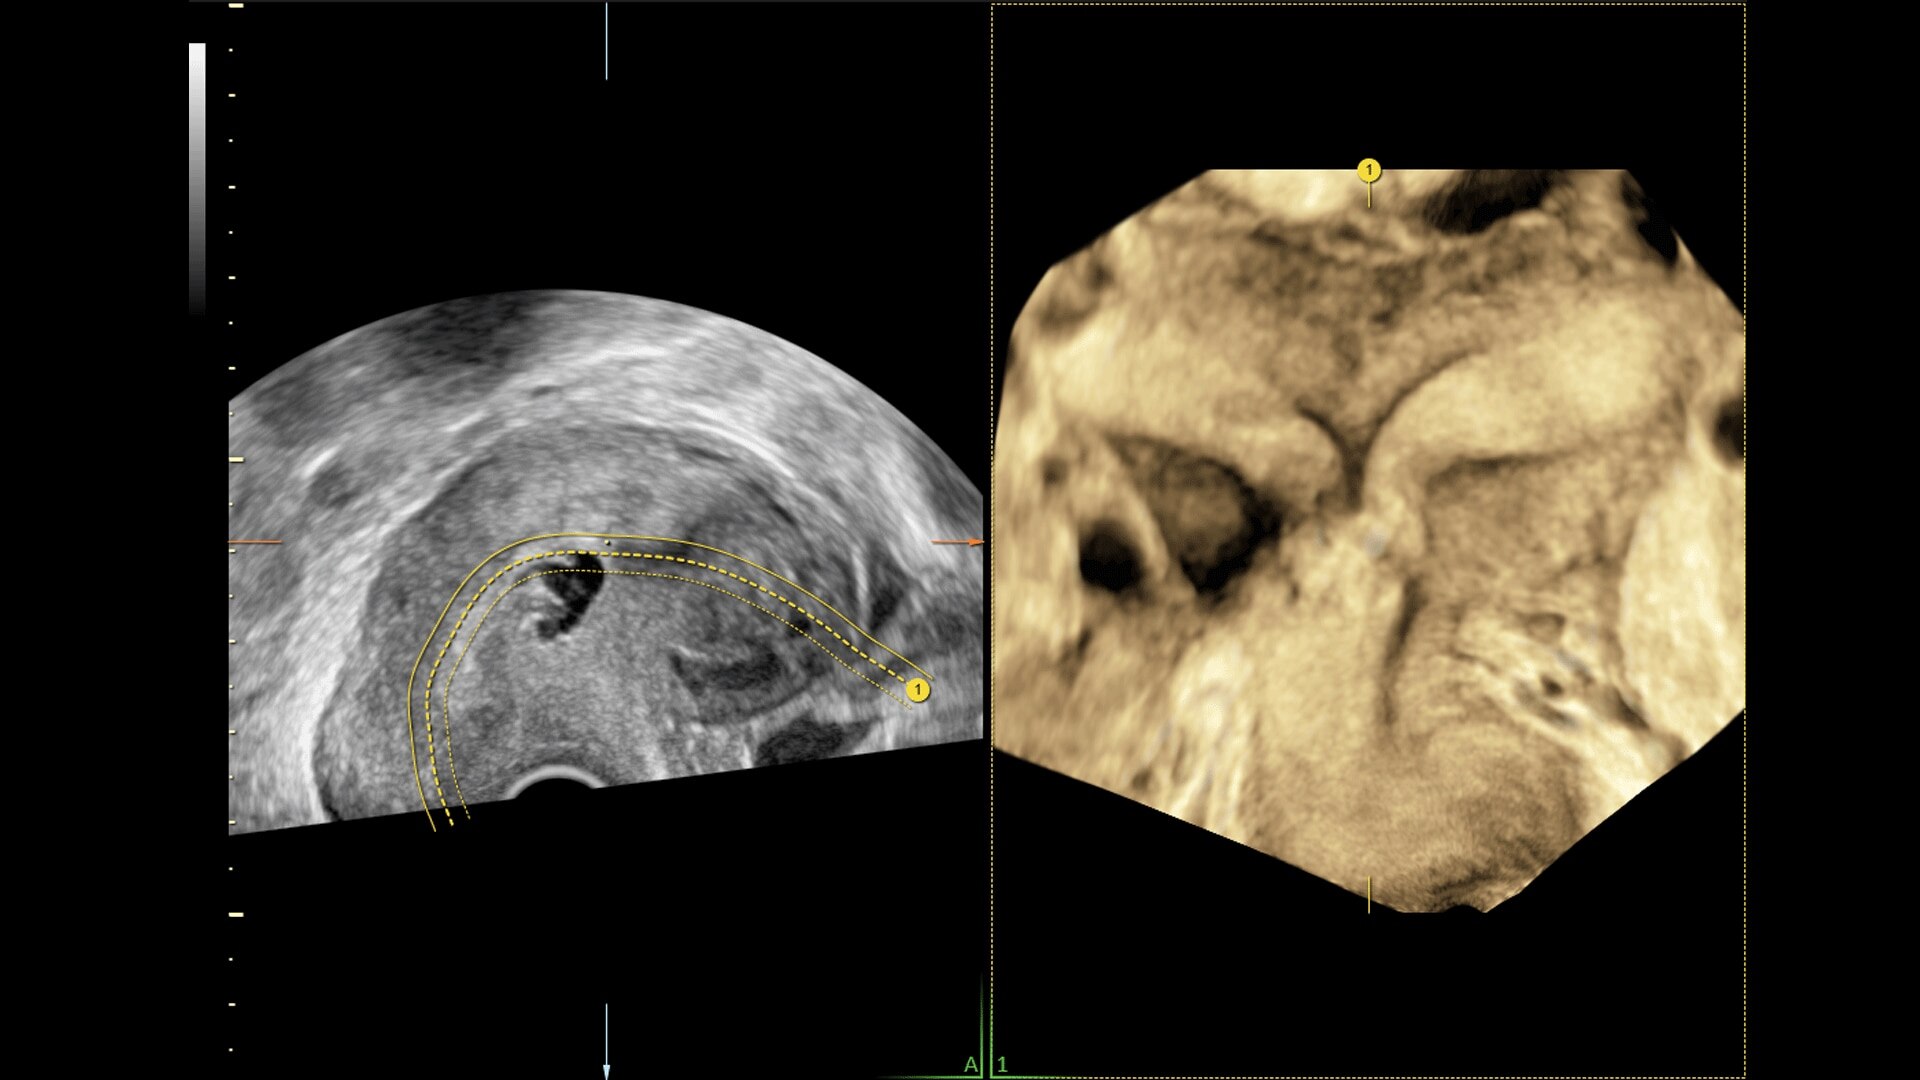

Generate spectacular 2D/3D and color Doppler images with increased penetration and stunning clarity, to help visualize critical details needed for diagnostic assurance. The Lyric Architecture unlocks new imaging and processing power to expand your imaging capabilities for years to come